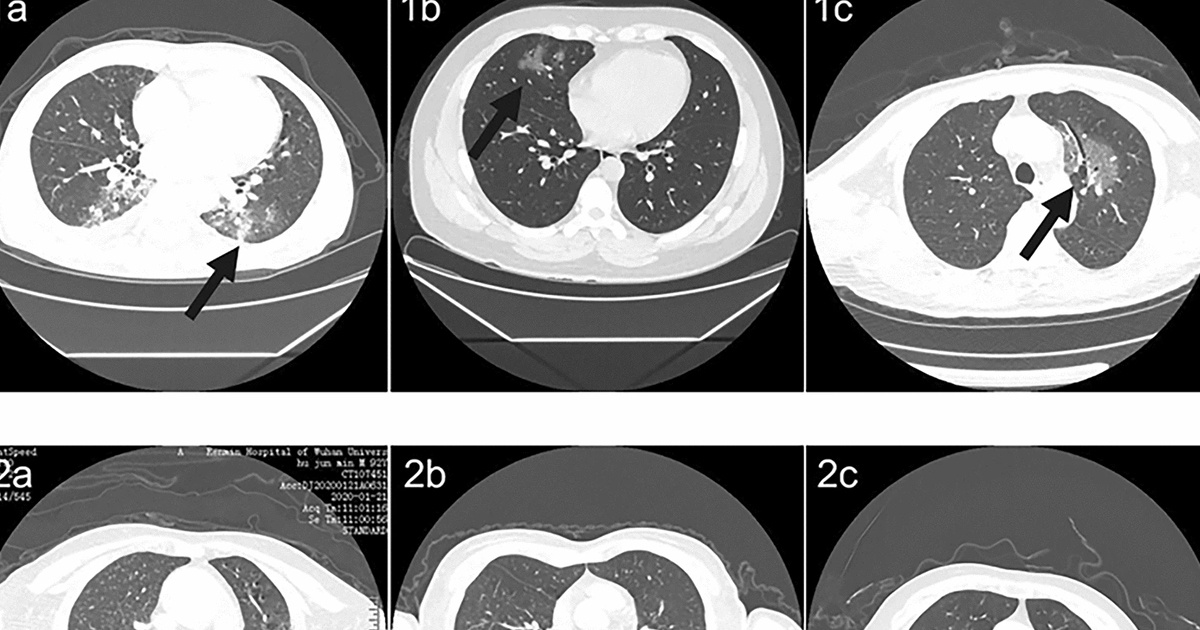

A través de tomografías computarizadas este método de diagnóstico a través de un algoritmo basado en aprendizaje profundo, investigadores planean desarrollar un sistema más eficaz que las técnicas tradicionales.

A través de tomografías computarizadas (TC), se obtienen la mayor parte de los diagnósticos de neumonía provocados por COVID-19. Ante ello, el objetivo del informe científico “Modelo basado en aprendizaje profundo para detectar neumonía por coronavirus nuevo de 2019 en tomografía computarizada de alta resolución” publicado en Nature, fue desarrollar un algorithm basado en aprendizaje profundo que permitiera detectar la neumonía relacionada a COVID-19 en TC de alta resolución. Para el desarrollo del modelo fueron recopiladas 46,096 imágenes de 106 pacientes del Hospital Renmin de la Universidad de Wuhan, incluidos 51 pacientes de neumonía por COVID-19.